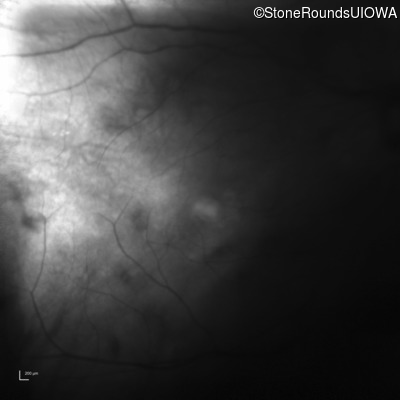

Infrared Fundus Photograph - Right - 20/40 +2

Exemplar